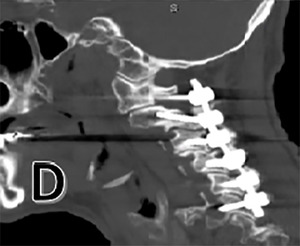

A post-operative CT scan is provided (Figure 1 D). The patient was placed in the ICU for post-operative monitoring. He tolerated the procedure well and his hospital course was uncomplicated. He was discharged in stable condition for a short course of inpatient rehabilitation.